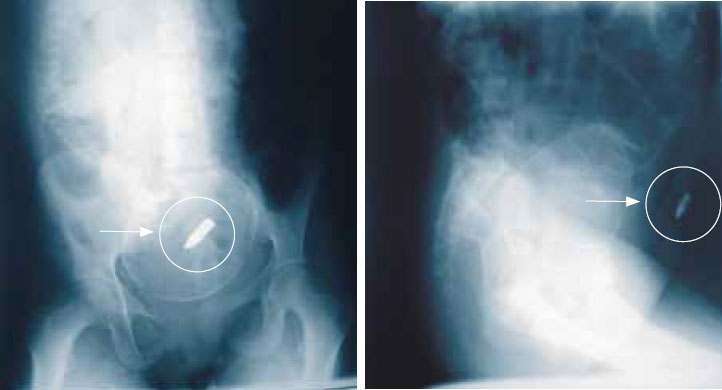

Тем не менее, как мы уже говорили, имеются показания к извлечению пуль и осколков, и эти показания можно подразделить на ранние и поздние. Наиболее важные ранние показания рассмотрены в статье «Военно-полевая хирургия: лечение ранений»: удаление инородного тела в процессе первичной операции и предупреждение опасности разрушения важной структуры (рисунок 1).

Рисунок 1. Пуля в матке с доношенным плодом

Рисунок 7. Пуля, расположенная экстрасиновиально вблизи бедренной кости